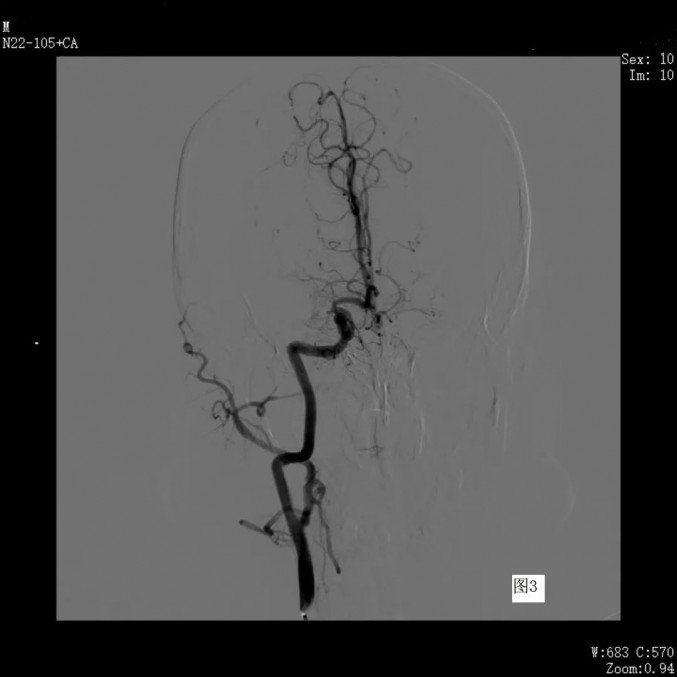

右侧颈内动脉造影见支架术后血管通畅良好(图3)